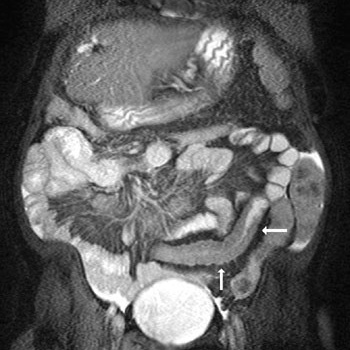

Resonancia nuclear magnetica de intestino delgado. EN. Codigo 883401-10 (2022)